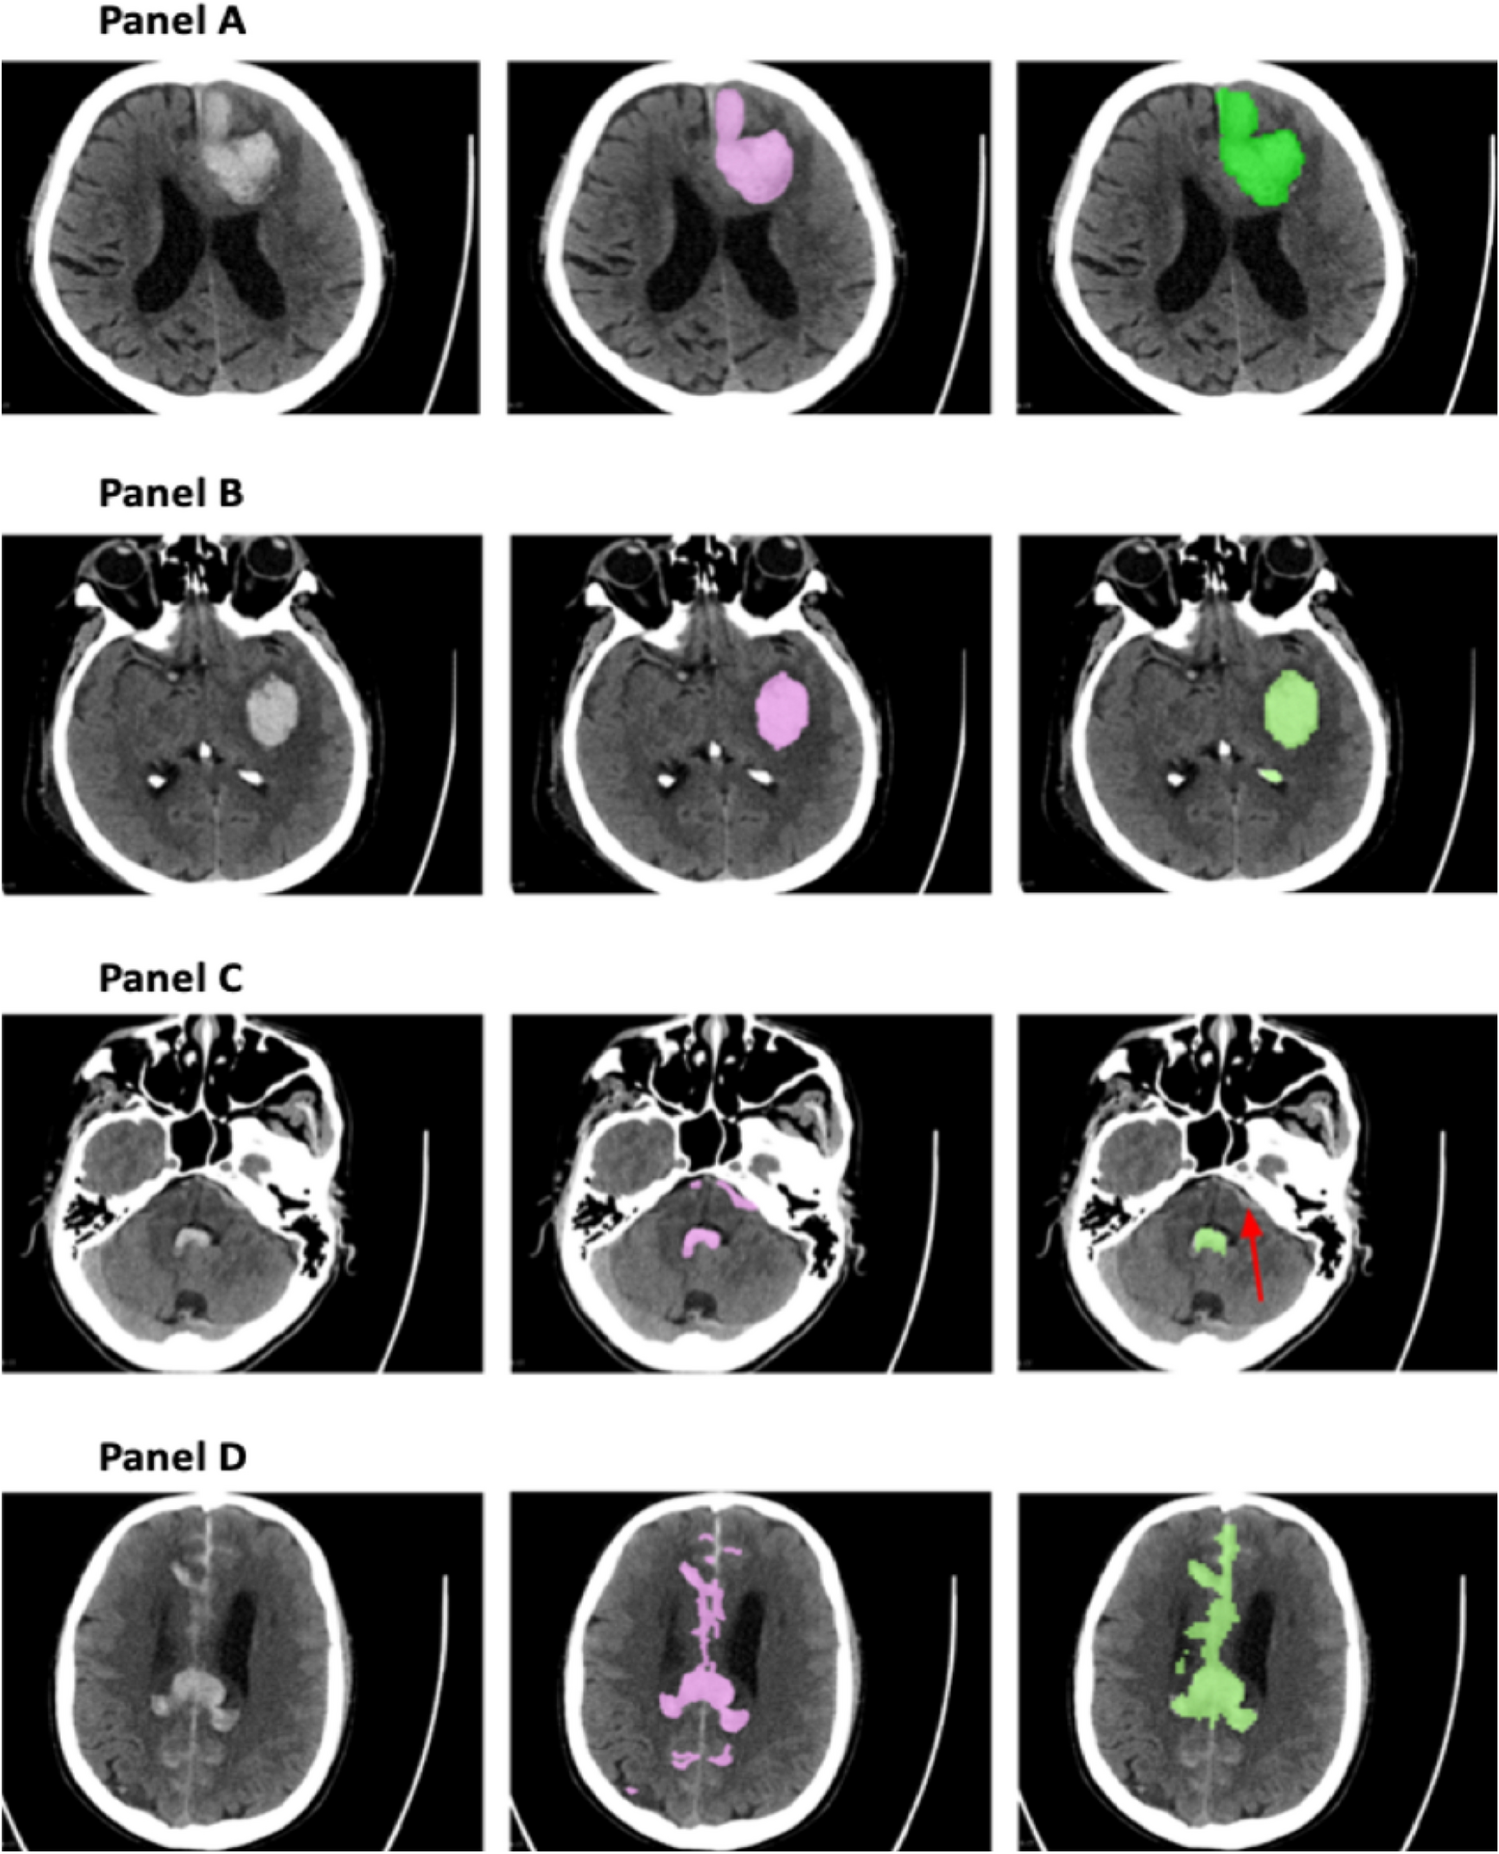

Figure 2

Examples showing the segmentation outcomes using the CNN-DS method. In each panel, the left, middle, and right images are the original CT slice, the ‘ground truth’ labels, and the CNN-DS predicted segmentation, respectively. The pointing arrows indicate the error. (A) Represents a case where the CNN-DS method demonstrates an expert-level performance. (B) Shows a false positive instance where a calcified structure is labelled as a hemorrhagic area due to its Hounsfield Unit values being higher than those of its surrounding tissues. (C) Shows a false negative example in which the CNN-DS method identified part of the hemorrhage but missed some blood close to the bone. (D) Illustrates a more complicated case of complex hemorrhage where the discrepancies between the ‘ground truth’ and the predicted segmentation cannot necessarily be attributed to erroneous prediction.